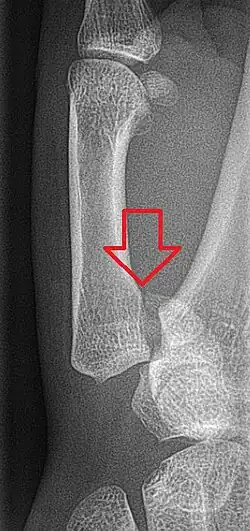

Rolando-Fraktur im Röntgenbild

Von der Bennett-Fraktur abzugrenzen sind Frakturen der Basis des ersten Mittelhandknochens, die nicht in das Gelenk ziehen (Winterstein-Fraktur). Eine Bennett-Fraktur mit einem Trümmerbruch wird als Rolando-Fraktur bezeichnet.